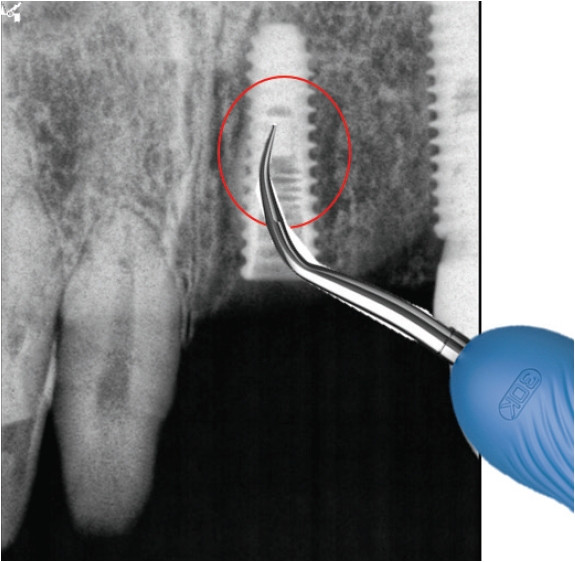

Fig. 2.

Trephine bur로 임플란트제거

1) 보철물연결나사 제거

임플란트연결나사는 보통 30N으로 채결되어 구강내에서 오랜기간을 유지하게 되는데 사용기간동안 반복되는 진동으로 풀리는 경우가 생길 수 있다. 이런 경우에는 보촐물의 동요도를 인지하게 되는데 서둘러서 치과를 방문하여 다시 조여주면 큰 문제가 없지만 방치하게 되면 피로파절이 발생하게 된다. 이때는 일단 먼저 보철물을 먼저 제거하고 파절된 나사를 제거하면 된다. 연결나사는 초음파기구로 역회전을 주면서 돌리면 조금씩 밀려나오게 되는데(Fig. 3) 이때 곧게 핀 익스플로러를 이용할 수도 있다(Fig. 4).

파절된 연결나사를 초음파기구로 역회전하면서 제거하기

jkda-2026-64-2-006f3.jpg